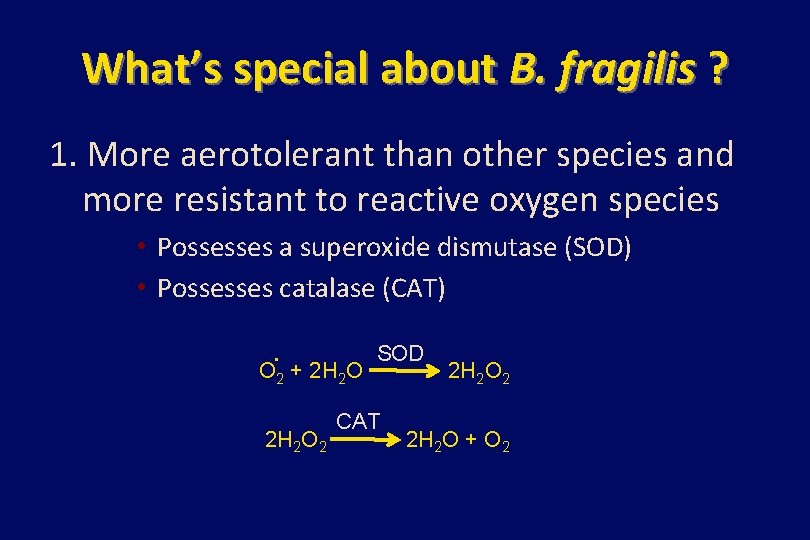

What’s special about B. fragilis ? 1. More aerotolerant than other species and more resistant to reactive oxygen species • Possesses a superoxide dismutase (SOD) • Possesses catalase (CAT) . SOD O 2 + 2 H 2 O 2 CAT 2 H 2 O 2 2 H 2 O + O 2